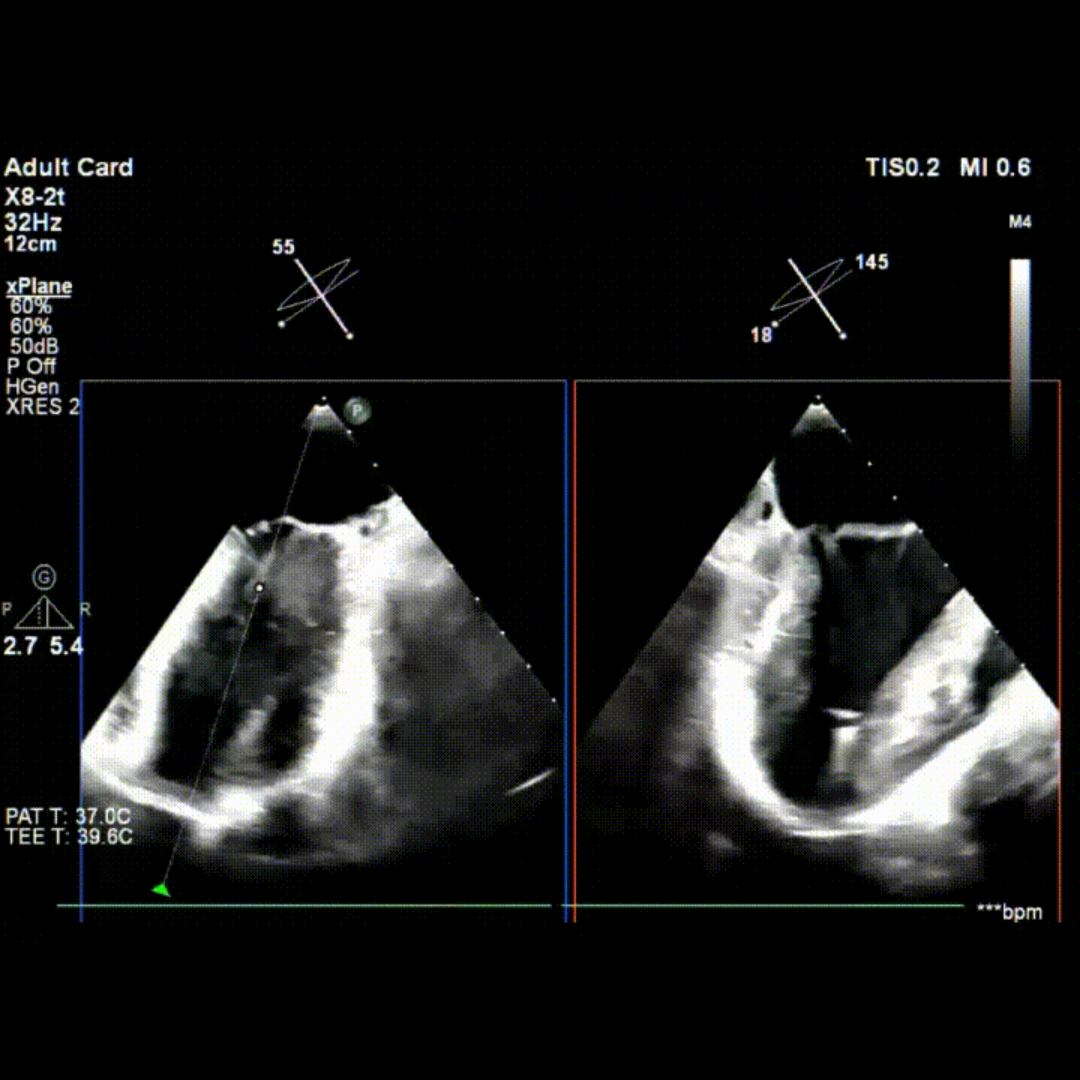

会议期间,张海波教授团队联合李伟教授完成了一例TA-TEER现场手术演示。患者为混合性二尖瓣反流(DMR+FMR),伴瓣环扩大、前瓣叶冗长、三区反流、后叶栓系及短小等复杂情况。术者在充分评估后选择置入双夹,手术获得圆满成功。现场专家就夹子型号选择、双夹放置位置及三区交界病变穿刺点等问题展开了深入讨论。

术前TEE影像

术中TEE影像